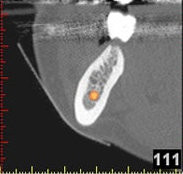

(siehe Bild 3 und 4).

Mit diesen gewonnenen Informationen und Planungen stellt der Zahnarzt interaktiv spezielle Bohrschablonen her. Diese ermöglichen eine exakte Positionierung der Implantate, so wie vorher am Computer geplant.